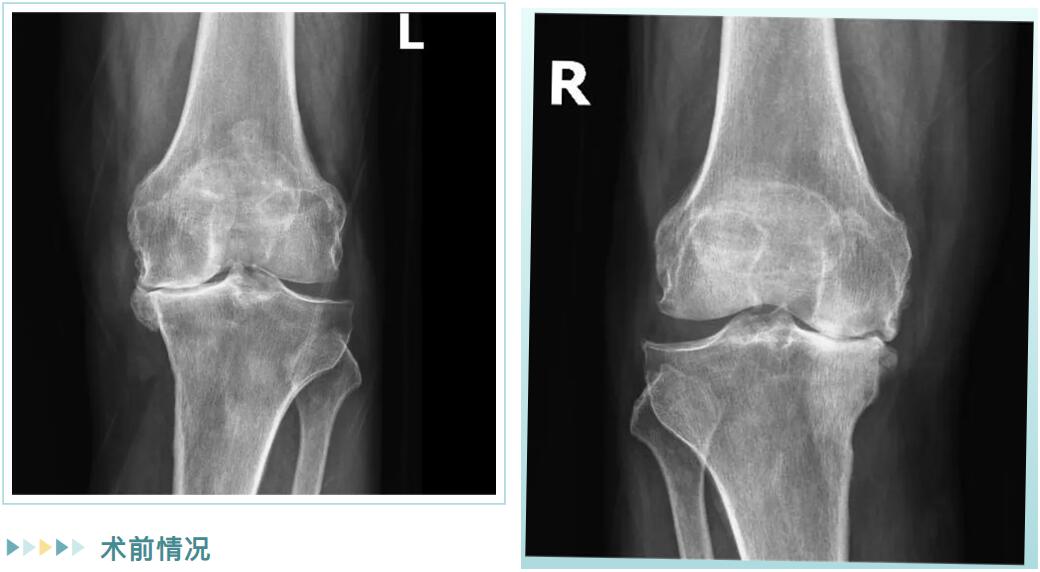

經(jīng)詳細(xì)檢查,邵阿伯被診斷為“雙膝重度骨性關(guān)節(jié)炎”。在保守治療無效后,羅院長團(tuán)隊(duì)為他量身定制了治療方案:雙側(cè)膝關(guān)節(jié)內(nèi)側(cè)單髁置換術(shù)。

術(shù)前情況